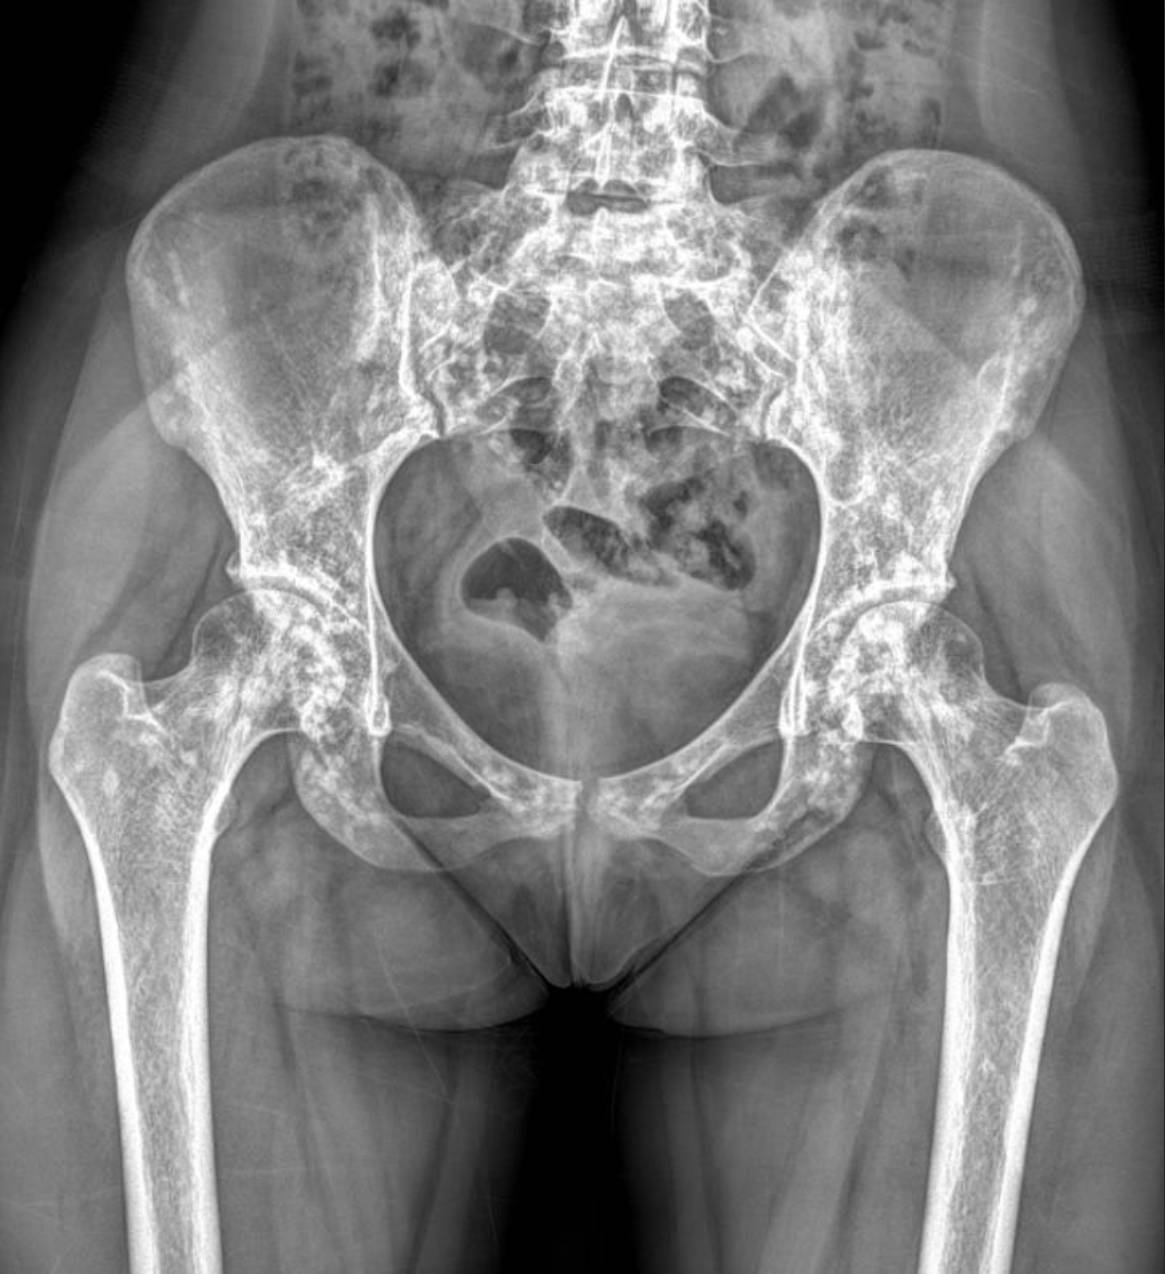

Radiological Findings: Skeletal X-rays (Incidental Discovery)

During the extensive workup for her hypertension and renal issues, skeletal X-rays were performed, which revealed a striking and unexpected finding.

The X-rays of the pelvis, knees, elbows, wrists, and ankles demonstrate multiple, discrete, well-circumscribed sclerotic (densely opaque) lesions distributed symmetrically throughout the bones. These lesions are typically ovoid or spherical, varying in size, and are predominantly located in the epiphyses and metaphyses of long bones, as well as in the carpal and tarsal bones and the pelvic girdle.

Specifically:

- Pelvis and Hips: Numerous small, dense, rounded opacities are scattered throughout the iliac bones, sacrum, ischium, pubic rami, and around the femoral heads and greater trochanters.

These widespread, symmetrically distributed sclerotic bone islands are pathognomonic for hereditary osteopoikilosis (also known as osteopathia condensans disseminata). This condition is typically benign and often discovered incidentally. While not directly related to her renal artery stenosis or hypertension, its discovery is crucial for patient management as it can sometimes be associated with other connective tissue disorders, though often it is an isolated finding.